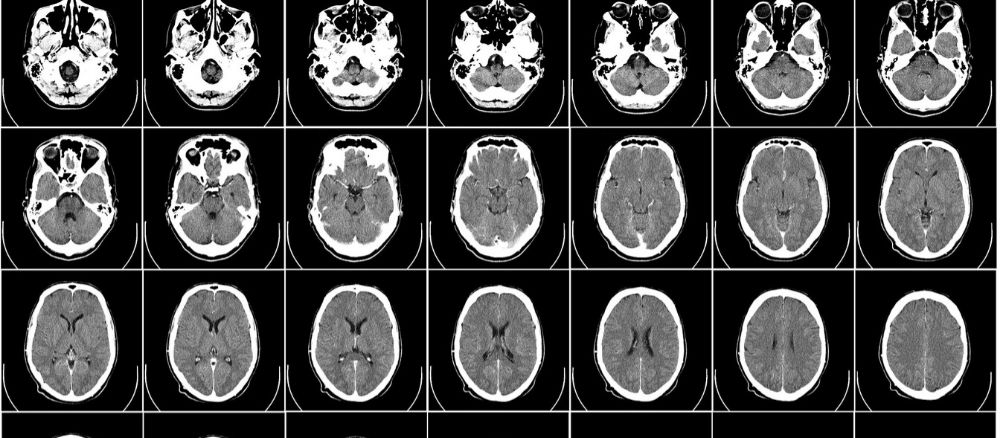

Alzheimer’s is a progressive neurodegenerative disorder that causes cognitive decline and memory loss. By peeping into the brains of various Alzheimer patients, the scientists zeroed in on the exact role of an anti-oxidant brain chemical called glutathione, which is known to protect the brain from stress. They studied the forms of glutathione and how its presence in different parts of the brain can help detect the early signs of mild cognitive impairment and Alzheimer’s.